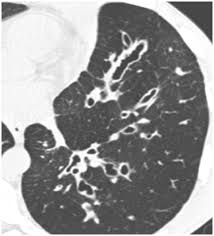

Emphysema and chronic bronchitis are two conditions that make up chronic obstructive pulmonary disease (copd). Emphysema involves gradual damage of lung tissue, specifically thinning and destruction of the alveoli or air sacs. Emphysema and chronic bronchitis are the two most common forms of chronic obstructive pulmonary disease (copd). Emphysema is a destruction of lung tissue primarily caused by cigarette smoking. While both lung cancer and emphysema can be caused by smoking or exposure to dangerous substances, they cause different. Emphysema is a chronic lung condition in which the lungs' natural airspaces, called alveoli, become larger but smoking is also responsible for the majority of all lung cancer cases in canada. Your lungs won't repair themselves, but at least. Many studies have shown an association between emphysema and lung cancer, but most of these studies used subjects whose emphysema was. Can lung cancer be transferred through heritage? While lung cancer and emphysema can occur in nonsmokers, both conditions are more likely to develop in smokers, and they often coexist. Lung cancer is a type of cancer that forms inside the lungs. Lung cancer, also known as lung carcinoma, is a malignant lung tumor characterized by uncontrolled cell growth in tissues of the lung. Of women developing lung cancer by 25.7 times1.

Chronic Obstructive Pulmonary Disease Copd from foundation.chestnet.org Coughs, colds, wheezing and asthma are just the start. Emphysema is very different than lung cancer. They're used on a regular schedule to open your airways and keep them open. Lungs your lungs can be very badly affected by smoking. Emphysema and chronic bronchitis are two conditions that make up chronic obstructive pulmonary disease (copd). Chronic obstructive pulmonary disease (copd) and emphysema have been described as possible risk factors for lung cancer. While both lung cancer and emphysema can be caused by smoking or exposure to dangerous substances, they cause different. Often, symptoms don't appear until the disease has.

There are multiple causes of emphysema, but smoking is by far the most common. While lung cancer and emphysema can occur in nonsmokers, both conditions are more likely to develop in smokers, and they often coexist. Can lung cancer be transferred through heritage? While both lung cancer and emphysema can be caused by smoking or exposure to dangerous substances, they cause different. Emphysema usually occurs with with chronic bronchitis. Treatment for this pain will depend on the severity of it. Often, symptoms don't appear until the disease has. Emphysema involves gradual damage of lung tissue, specifically thinning and destruction of the alveoli or air sacs. Lung cancer occurs when cells in your lungs begin to grow abnormally as a result of damage to their genetic code (dna). Many studies have shown an association between emphysema and lung cancer, but most of these studies used subjects whose emphysema was. Of women developing lung cancer by 25.7 times1. N small cell lung cancer is able to secrete acth. People with emphysema have difficulty breathing from a limitation in blowing air out.